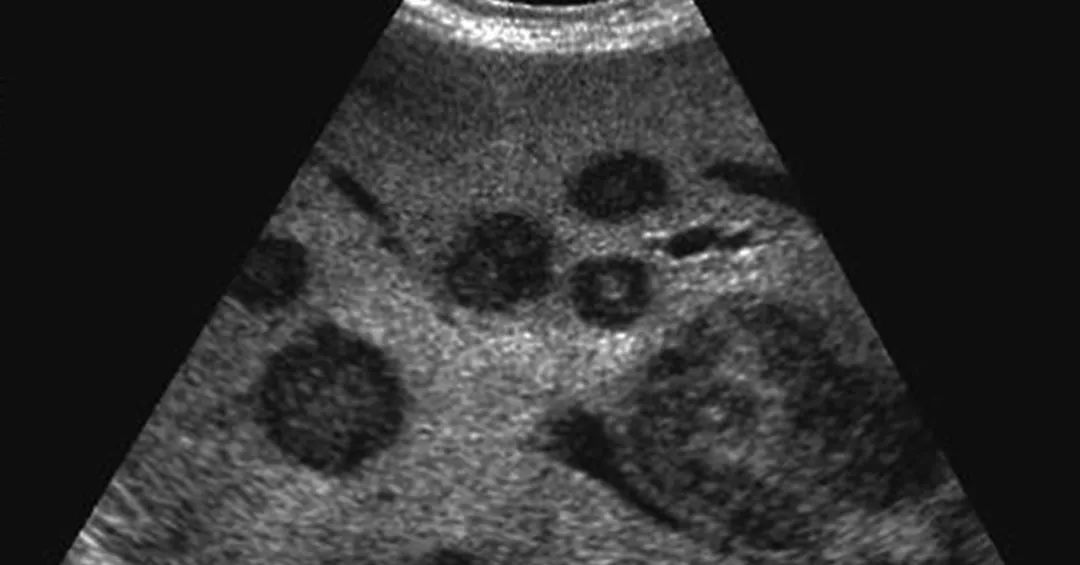

10种肝脏疾病超声诊断

图片尺寸608x414